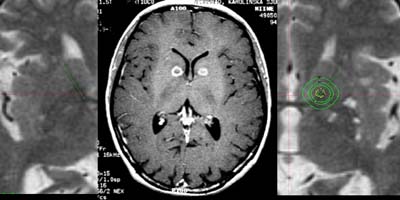

³úµ¿Á¤¸Æ

񃀁

³ú

±íÀº °÷¿¡ À§Ä¡ÇÏ¿© ³úÃâÇ÷À» ÀÏÀ¸Å² 17¼¼

¿©ÀÚȯÀÚÀÇ MRI ¹× ³úÇ÷°üÃÔ¿µ¼ú »çÁø.

³úÀÇ

±íÀº °÷¿¡ ³úµ¿Á¤¸Æ±âÇüÀÌ À§Ä¡ÇÏ¿© ¼ö¼úÀû

Ä¡·á°¡ ºÒ°¡´ÉÇÏ¿´À¸³ª °¨¸¶³ªÀÌÇÁ ½Ã¼ú

ÈÄ 24°³¿ù°¿¡ ¸ðµÎ ¿ÏÄ¡µÇ¾ú´Ù

°æ·ÃÀ»

ÁÖ¼Ò·Î ÀÔ¿øÇÑ È¯ÀÚÀÇ MRI ¹× ³úÇ÷°üÃÔ¿µ¼ú

»çÁø.

µ¿Á¤¸Æ±âÇüÀÇ

Å©±â°¡ Ä¿¼ ¼ö¼úÀÇ À§Ç輺ÀÌ ³ô¾Æ °¨¸¶³ªÀÌÇÁ¸¦

°èȹÇÏ¿´´Ù. º´º¯ÀÇ Å©±â°¡ Ä¿¼ °¨¸¶³ªÀÌÇÁ

¹æ»ç¼±¼ö¼úÀ» ¸îÂ÷·Ê¿¡ ³ª´©¾î¼ ½ÃÇàÇÏ·Á

ÇÏ¿´À¸³ª ÇÑÂ÷·ÊÀÇ °¨¸¶³ªÀÌÇÁ ½Ã¼ú ÈÄ

24°³¿ù° ¸ðµÎ ¿ÏÄ¡µÇ¾ú´Ù.